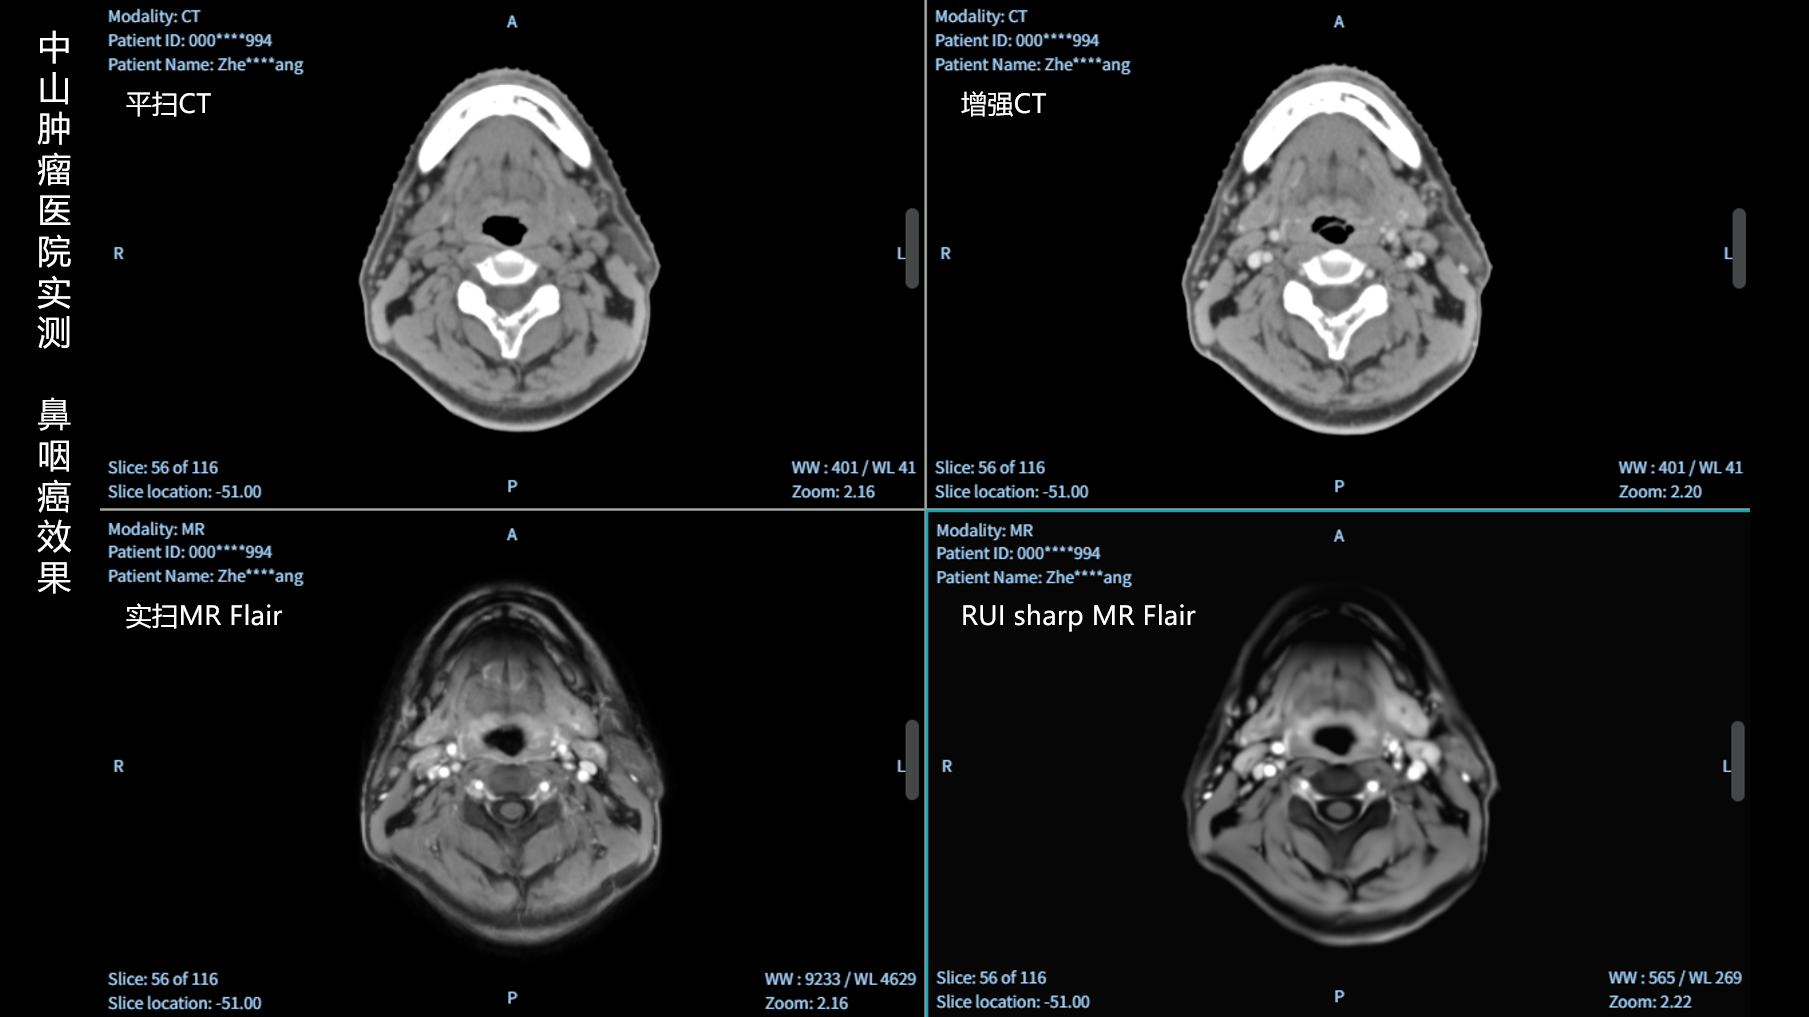

RUI sharp H(锐影)可在不依赖MRI的前提下,显著提升头部CT图像的软组织分辨率,为临床提供更高质量的辅助信息,尤其适用于MRI资源受限或较难配准的头颈部放疗感兴趣区勾画场景。

可大幅提高头部CT影像软组织分辨率,使肿瘤和周边器官显示更清晰,为放疗靶区勾画提供参考。

无需图像配准,CT和锐影图像同源,可匹配、叠加、"淡入淡出"显示。